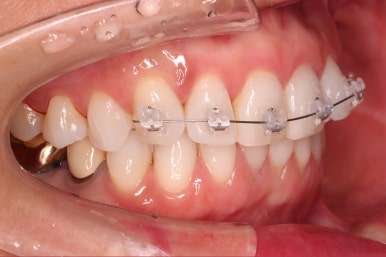

초진 시 입안의 모습입니다.

환자분이 원하셨던 부분은 윗니 작은 앞니가 하나 튀어나와서 개선하고 싶어하셨습니다.

부가적으로 아랫니 앞니가 마모가 심하여 높낮이가 달라보이는 점이었는데요.

윗니에만 장치를 부착하고 부분교정을 시작했습니다.

환자분이 연산동부분교정 선택하신 장치는 엠파워 클리어라고 하는 자가결찰 세라믹 장치입니다.

장치 부착한 모습 참고해 주시고요.